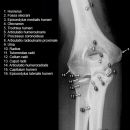

Ellenbogen seitlich (2. Ebene radio-ulnar)

Beurteilungskriterien

- Weichteilzeichen: Verlagerung des ventralen (proximal der Fossa coronoidea bis 5mm breit ist normal) und dorsalen distalen Humerusfettkörpers (normalerweise nicht sichtbar), Supinatorfettlinie: normalerweise etwa 3-4cm lang und 2-3mm breit, parallel zum proximalen Radius

- Target areas: vordere und hintere Humeruskontur, Radiusköpfchen, Processus coronoideus (evtl. zusätzlich 45°-Schrägaufnahme), Olecranon, harmonische Darstellung des Radiusköpfchen? Impressionen? Stufe? Verdichtungen, Fissur? Knickbildung?

- Auftreten, Verschmelzung und Lokalisation der Epiphysenkerne -> Verlagerung? vgl. Anatomie Kids! Viele kindliche Verletzungen sind anhand der Verlagerung der Knochenkerne differenzierbar! Evtl. Vergleich mit Gegenseite oder MRT hilfreich.

- Täuschungsmöglichkeiten: Persistierende Apophysen an Olecranonspitze oder Processus coronoideus, Kortikaliseinkerbungen als Residuen der Epiphysenfugen (v.a. des Olecranons)

- Kids: Kreuzung vordere Humeruslinie mit Radiushalsachse im mittleren Capitulumdrittel? Abweichung -> dislozierte, supracondyläre Humerusfraktur? Epiphysenfugenverletzung? Dislokation des proximalen Radius? Luxation?

Cave:

- 50% der Radiusköpfchenfraktur sind nicht disloziert und u.U. nicht nachweisbar -> bei klinischem Verdacht ist ein positives Fettpolsterzeichen nahezu beweisend! Greenspan-Aufnahme, evtl. CT oder MRT!

- Distale Humerusfraktur (Trochlea oder Capitulum) mit frontaler Bruchebene -> "Halbmondzeichen" durch plankonvexe(s) und in die Fossa cubiti dislozierte(s) Fragment(e) -> CT zur Beurteilung der Gelenkflächenverhältnisse.

- Komplexe Frakturen, Gelenkflächenverhältnisse? -> CT